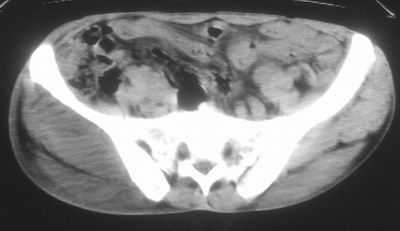

标题: CT16837:M63Y,右臀部巨大软组织包块 [打印本页]

标题: CT16837:M63Y,右臀部巨大软组织包块

患者,男,63岁,自诉3个月前发现右臀部包块,触及疼痛,治疗后缩小。前天突然增大。无高热病史。

给个骨窗,判断一下肿块是否与髂骨有关,肿块内出血是肯定的,至于是感染形成的脓肿还是起源于肌肉或纤维组织的肉瘤则难以确定,不过从影像上看,包膜完整,且环形增厚,病灶下部见斑片状底密度坏死,个人倾向感染可能性大

肌间隙明显混浊,三个月前治疗有缩小,支持考虑臀大肌下脓肿伴出血,肿瘤如果出现瘤内出血的话瘤外边界应该较清楚,现在表现为一种恶性征像,但骨质无明显异常,且臀小肌边界清楚,不符合恶性表现.